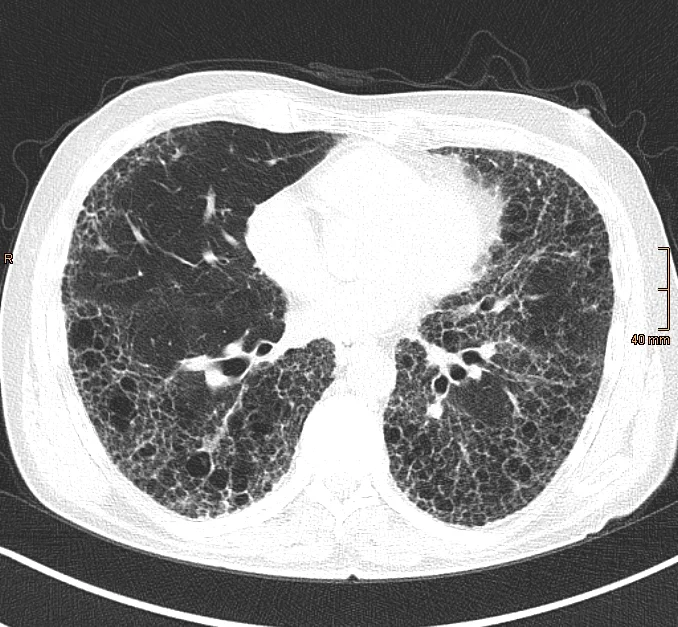

Der radiologischen Bildgebung mittels HRCT ist hierbei von zentraler Bedeutung. Es handelt sich hierbei um eine spezielle Form der Computertomographie (CT), bei der besonders hoch aufgelöste Bilder und dünne Schichten der Lunge erstellt werden. Als "Honeycombing" (Honigwabenmuster) wird hierbei ein fortgeschrittenes Stadium der Erkrankung beschrieben, bei dem das Lungengewebe durch Vernarbung so stark verändert ist, dass es einer Honigwabe ähnelt.

Man sieht hier das typische Bild einer IPF (idiopathischen Lungenfibrose) mittels HRCT und dem klassischen UIP-Muster: supleurale und basale Prädominaz, retikuläre Veränderungen, Honigwaben ("Honeycombing"), Traktionsbronchiektasen